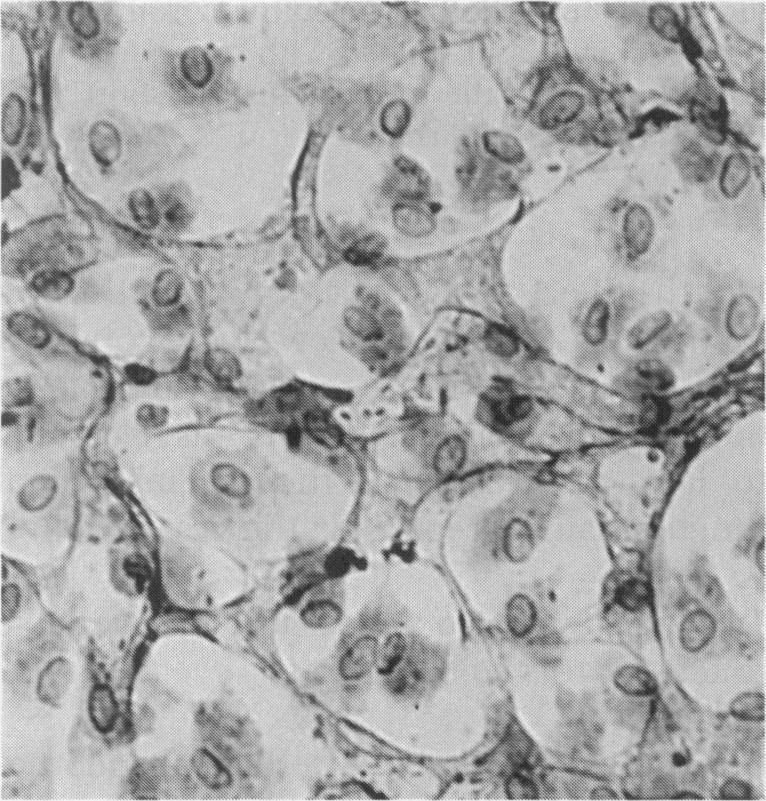

Immunocytochemistry has been used to identify endothelial cells in sections of human umbilical cord and in cultures of the venous and arterial endothelium, using Factor VIII and Ulex europaeus as endothelial markers. The connective tissue components, including various collagen types, fibronectin and laminin, were identified and localized in the cord and in both venous and arterial cultured endothelium. Interstitial collagens synthesized by the cultured cells were isolated and quantified. Angiogenic ability was examined. The effect of a noxious stimulus, 24 h hypoxia, was quantified in cultured venous endothelium. The results showed that cultured arterial endothelium possesses a vacuolated cytoplasm which is absent in venous endothelium. The major collagens observed in venous culture were types III and V; the latter was found mainly in the cell layer. Venous endothelium was angiogenic. It responded to hypoxia by producing fewer cells, more protein/10(6) cells but less collagen, both in absolute terms and as a percentage of protein/10(6) cells, thus behaving like cultured porcine and bovine aortic endothelium. Fibronectin was the major 'glue' associated with endothelium. We conclude that culture can reveal the synthetic potential of endothelium which the cord itself does not often show; moreover culture appears essential to demonstrate that arterial and venous endothelium behave differently from each other.